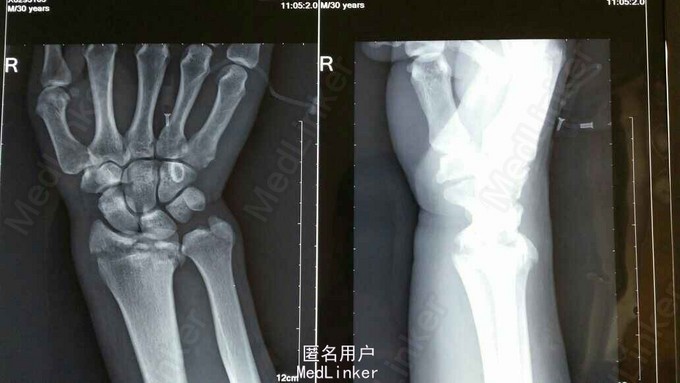

患者于2015年8月18日从高处坠落(约7米)伤及双碗,肿胀,畸形,活动受限。

双碗畸形明显,肿胀明显,可见明显皮下淤血,压痛阳性,可触及明显骨察感及骨察感,左手有明显正中神经压迫症状。

诊断:双尺桡骨远端粉碎性骨折 治疗:入院后,给予手法复位夹板固定,左手神经症状明显缓解,给予对症治疗,消肿后,于2015年8月27日行手术治疗。